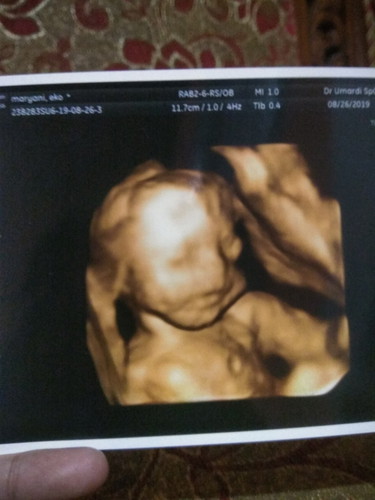

Bunda2 mau tanya semalam saya USG kata dokter nya usia kehamilan nya 5bulan stngah Kalo di bidan sdh 6bulan Kondisi bayi nya Alhamdulillah bgus semua Bun gak ad keluhan ap2,, Nah saya masih bingung Bun banyak orng2 bilang saya gemuk banget,, Tinggi badan saya 155 sblum hamil BB sya 45 Bun Di usia kehamilan skrng 60kg,, Normal gak bun? Atau emng kegemukan